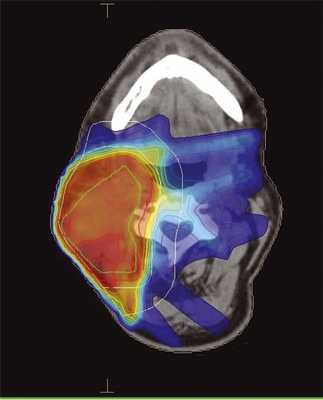

Больной С., 1951 года рождения, проходил лечение в клинике МРНЦ им. Цыба в январе 2010 г. с диагнозом: плоскоклеточный рак гортани cT2N2M0. Проведен радикальный курс одновременной химиолучевой терапии, в конвенциональном режиме РОД 2 Гр до СОД 60 Гр. После окончания лечения выявлена остаточная опухоль в лимфатических узлах шеи, однако больной категорически отказался от операции. В мае 2014 г. отметил бурный рост лимфатических узлов, но за помощью обратился только в декабре 2014 г. Проведен курс повторной конформной лучевой терапии в режиме гипофракционирования РОД 3 Гр до СОД 45 Гр (EQD2 =54 Гр), с одновременной химиотерапией (цисплатин). Больному предварительно была проведена реконструкция ранее полученных доз, не выявившая превышения значений толерантности (табл. 3). При этом была выбрана методика IMRT, поскольку это позволяло в значительной степени снизить нагрузку на ранее облученную гортань (рис. 3).

Рис. 3. Дозное распределение при повторном облучении очага в носоглотке методикой IMRT. Градиентом цвета обозначен переход от максимальной дозы (красное) к минимальной (синий цвет, 10% от максимальной). Покрытие мишени (PTV) не менее 95%.

В настоящее время больной наблюдается в течение полугода, имеется остаточное образование в лимфатических узлах шеи, однако по результатам проведенного ПЭТ/КТ уровень накопления радиофармпрепарата является неспецифичным (2,7 SUV ед.). Острые лучевые реакции во время лечения были умеренными (мукозит 2-й степени, дерматит 1-й степени). Признаков поздней лучевой токсичности не отмечено.